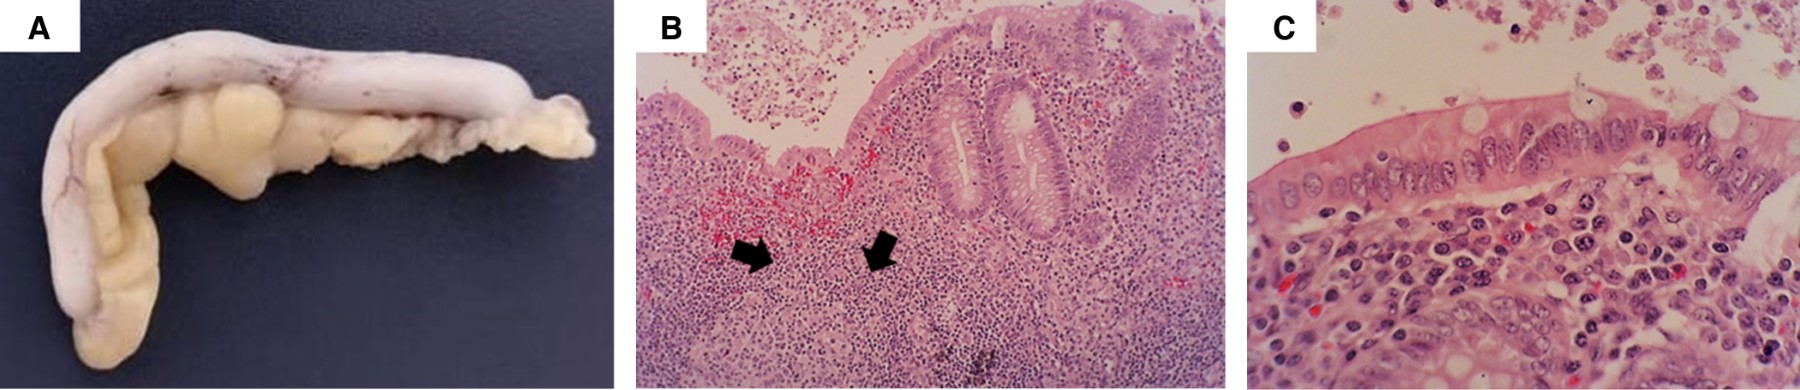

Los estudios de laboratorio fueron los siguientes: hemoglobina 10.5 g/dL, leucocitos 25,050/mm3, neutrófilos 23,050/mm3 (90%), linfocitos 1,400/mm3, bandas 3%, plaquetas 9,000/mm3, proteína C reactiva (PCR) 18 mg/dL, velocidad de sedimentación globular (VSG) 12 mm/h, procalcitonina 32.75 ng/dL, fibrinógeno 143 mg/dL, dímero D 10,594 ng/mL, ferritina 7,540 ng/dL, NT-proBNP 69,530 pg, troponina I 1,420 ng/L, triglicéridos 746 mg/dL, bilirrubina total 3.21 mg/dL, bilirrubina directa 2.14 mg/dL, aspartato aminotransferasa (AST) 294 UI/L, alanino aminotransferasa (ALT) 69 UI/L, deshidrogenasa láctica (DHL) 921 UI/L, albúmina 2.2 g/dL, pH arterial 9.19, lactato 8, bicarbonato 13. Con el hallazgo quirúrgico negativo a apendicitis, marcadores de inflamación grave y el antecedente de COVID-19 reciente en la madre (mediante RT-PCR nasal) se hizo el diagnóstico de MIS-C. En la exploración física además de la inyección conjuntival y lengua en fresa, se encontró esplenomegalia. Se inició tratamiento con gammaglobulina intravenosa (IgIV) 2 g/kg y bolo intravenoso de metilprednisolona (30 mg/kg). A pesar del inicio de tratamiento, la evolución fue tórpida, con la sospecha de SAM por HScore de 294 puntos, se realizó aspirado de médula ósea que mostró células hemofagocíticas (Figura 2), no tuvo respuesta al manejo, presentó disfunción miocárdica y falleció a las 12 horas de su llegada al hospital.

Figura 1

Figura 2